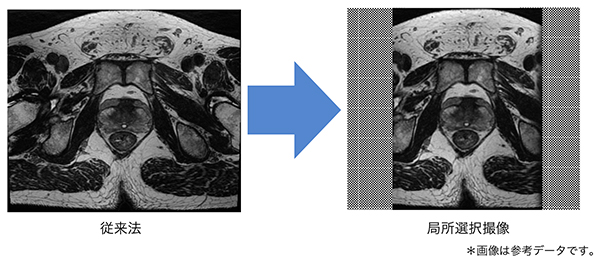

HyperCube(ハイパーキューブ)

ボリュームイメージング法に局所撮像技術を応用し,位相方向のFOVを小さくすることで撮像時間を大幅に短縮します。特殊な抑制パルスを用いることで折り返しアーチファクトの影響が無く,HyperSenseと併用をすることで高分解能ボリュームスキャンがさらに短い時間で得られます。